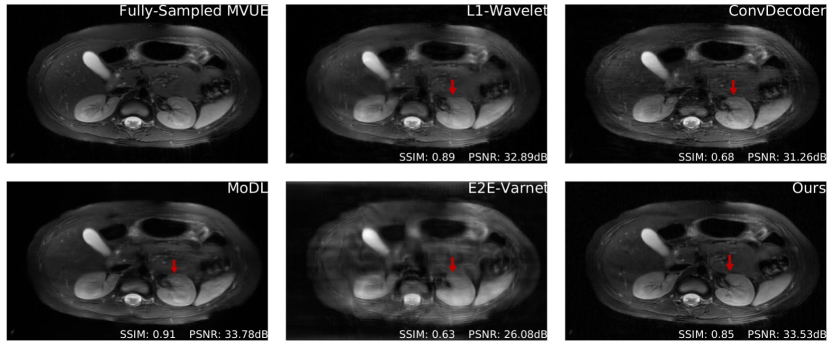

Refer to caption

Figure 3: Comparative reconstructions of a 2D abdominal scan with uniform random under-sampling in the horizontal direction at R=4𝑅4R=4. None of the methods were trained to reconstruct abdomen MRI. Our method uses a score-based generative model trained on brain images (as explained) and obtains good reconstructions. The red arrows indicate missing details or artifacts in the kidney structure.

Figures 2c & 5c show PSNR and SSIM scores obtained on reconstructed abdominal scans obtained from [1] at different acceleration factors. This represents both an anatomy and sampling pattern shift, and it can be seen that our method, MoDL, and the 1subscript1\ell_{1}-Wavelet algorithm retain their competitive advantage, while the ConvDecoder and E2E-VarNet suffer severe performance losses. Figure 3 further shows a qualitative comparison of a reconstructed abdominal scan at R=4𝑅4R=4, with highlighted artifacts. Appendix E shows another abdomen scan.